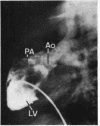

The clinical and anatomical findings in two patients with isolated ventricular inversion and situs solitus are described. The other 4 previously published cases are reviewed. The 6 patients with this malformation, all without pulmonary stenosis, presented a clinical picture of cyanotic congenital heart disease, associated with increased pulmonary blood flow (hypoxaemia and cardiac failure). The importance of different diagnostic tests is discussed and it is concluded that angiocardiography is the only definitive means of establishing the dianosis. Because the physiopathological disturbance is the same as in transposition of the great arteries, both malformations should be similarly considered with respect to diagnosis and treatment. Nevertheless, the high incidence of certain associated malformations in cases of isolated ventricular inversion adds to difficulty in diagnosis, and makes a good result from the Mustard procedure less likely than in transposition of the great arteries.